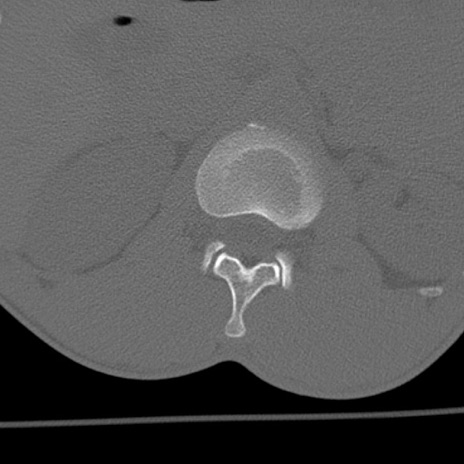

症例3 腰椎CT(横断像)

腰椎CT